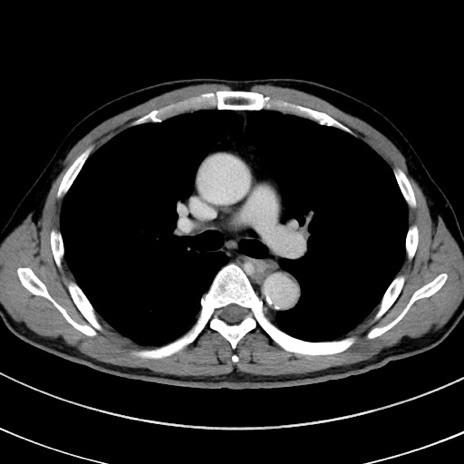

冠状断像

【症例】 60歳代男性

【主訴】 黒色吐物

【現病歴】 4日前から嘔気自覚、2日前の朝食後にも嘔気あり、自分で手で嘔吐反射起こし嘔吐したところ血が混ざっていたため受診。

【既往歴】 5年前汎発性腹膜炎を伴う急性虫垂炎で手術、高血圧、前立腺肥大症、高脂血症

【身体所見】 腹部正中に手術癩痕あり 腹部平坦・軟圧痛なし膨満感あり

【データ】WBC 8400、CRP 4.54